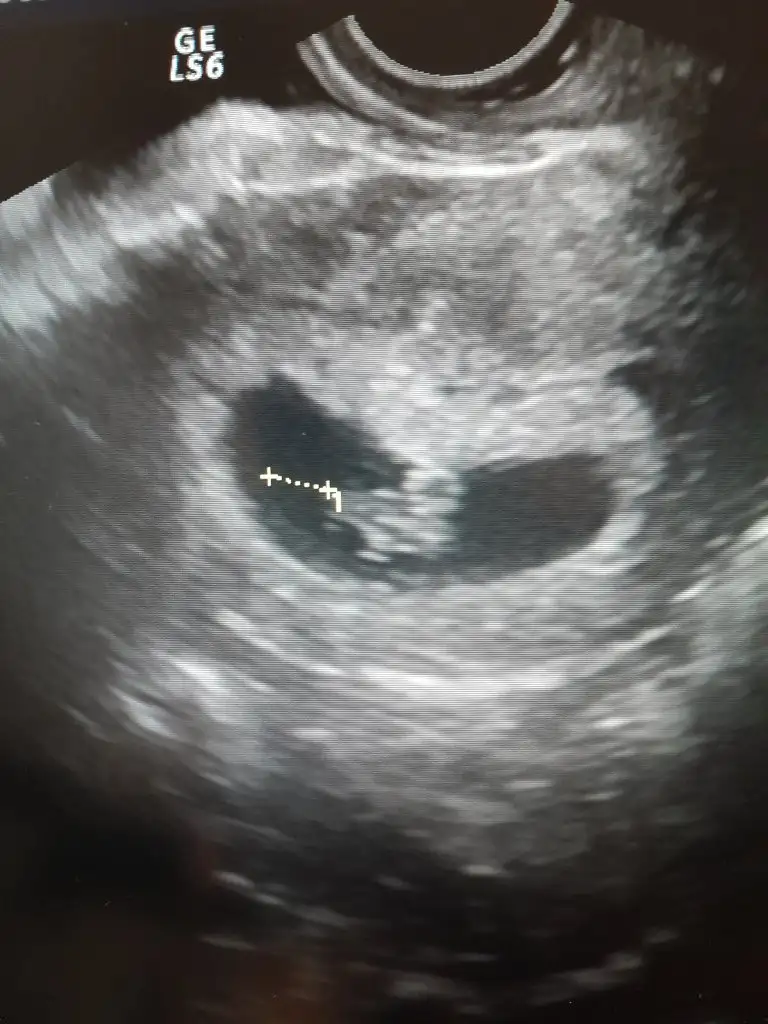

Erkek gibi cnmEki Görüntüle 3285243 13 haftalık sizce cinsiyeti nedir

Kız bebekMerhaba arkadaşlar . Bir arkadaşımın 13 haftalık usg görüntüsü . Rica etsem tahmin eder misinizEki Görüntüle 3279119